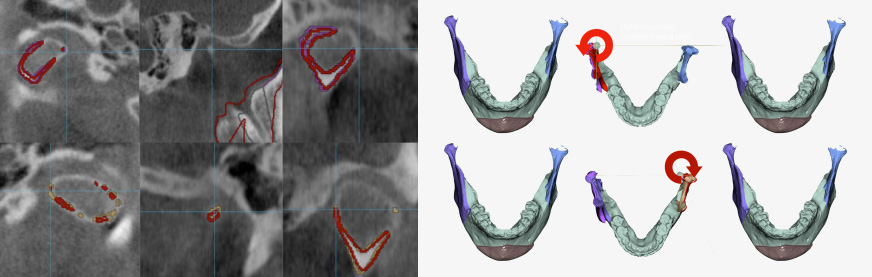

CBCT Reorientation

- Successful surgery requires accurate preoperative diagnosis & precise surgical planning

- CBCT analysis errors caused by slight patient movement can have significant impact on final surgical outcome

- Reorientation function corrects any patient position error during CBCT scan to provide best data for precise diagnosis

Jaw segmentation

- Skull data can be freely osteotomized according to technique preferred by oral surgeon

- Osteotomy position, range, & amount can all be adjusted depending on patient characteristics

- Combining osteotomy segments verifies anatomical changes during bone deletion & bone movement for feasible & precise surgical plan

3D Jaw Setup & Review

- Send R2 STUDIO data & simple surgery plan to R2 Center & receive 3D jaw setup file within 24 hours

- Use FACEGIDE review program to confirm 3D jaw setup file

TMJ Position Control

- Condylar position can be adjusted after surgery

- Minimizes any side effects due to changes in TMJ position